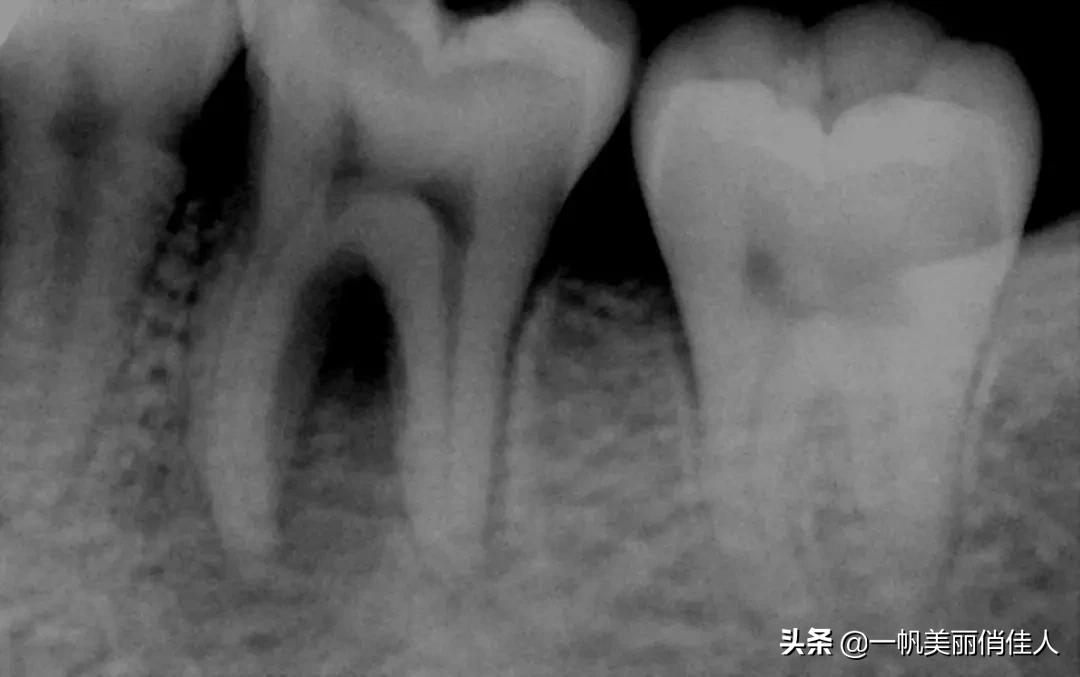

所以,最好先去医院检查一下,医生一般会通过做X光片来检查恒牙是否埋伏在牙床里,以及是否存在发育上的问题。

换牙期的儿童牙齿和成年人的恒牙图:换牙时,乳牙的牙根会主动溶解,恒牙则会从下方长出,另外增加的侧门齿和臼齿会从颌骨中萌发